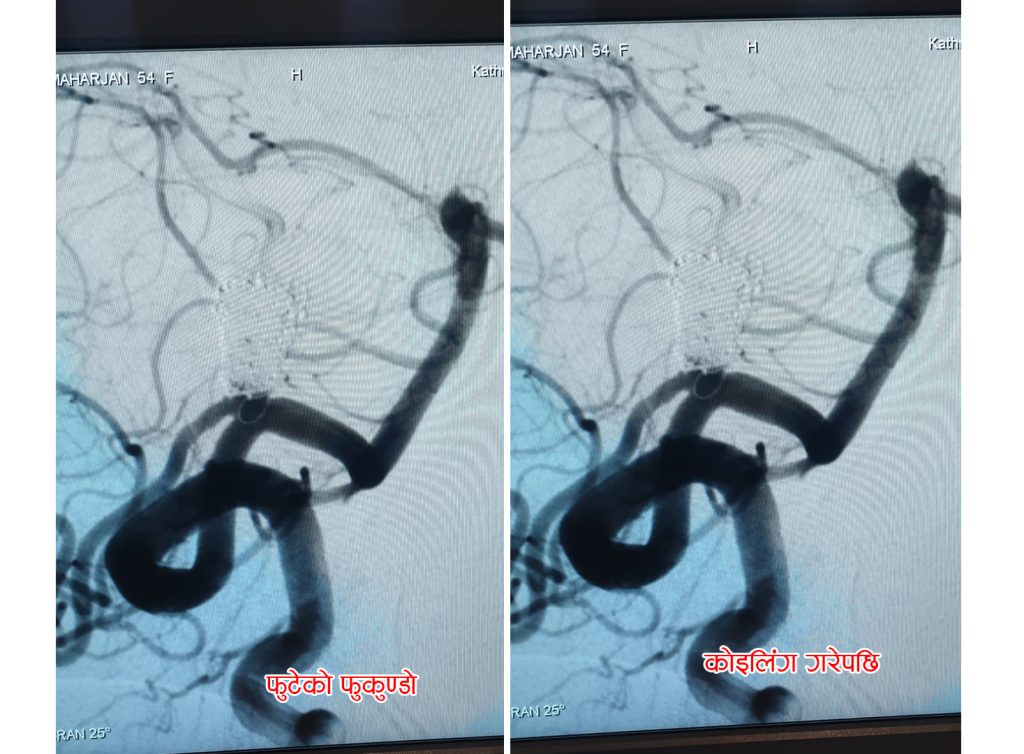

ब्रेन हेमोरेज-सबएरेकनोइड हेमोरेज भएर आएकी ती महिलाको रक्तनलीबाट मस्तिस्कमा पुगेर ब्लक भएको रक्तनली खुलाइएको इन्टरवेंशनल न्यूरोलोजिस्ट डाक्टर समर्थ सिंहले जानकारी दिए । ‘एक महिना अगाडी उहाँलाई ब्रेन ह्याम्रेज भएर केएमसीमा ल्याइएको थियो । बिरामीको ब्रेनको पछिलो भागको रक्तनलीमा फूकुन्डो, जसलाई ब्रेन अनेउरीसम भनिन्छ, फुटेर मस्तिस्कमा रक्तस्राव भएकाे थियो । हामीले न्युरो इन्डोभास्कुलर कोइलिङ प्रविधिबाट बिरामीको टाउको नचिरीकन सफलतापूर्वक कॉइलिंग पद्धतिबाट सो फुटेको फुकुन्दोमा रक्तप्रवाह बन्द गरेर सफलतापूर्वक उपचार गर्यौं ।’ डा. सिंहले भने ।

न्यूरो इन्टरवेंशनल प्रविधिमा बिरामीको तल्लो पेट, तिघ्राको बिचको भाग अथवा नाडीसँगै भएको रक्तनलीबाट मुटुभन्दा माथि रक्त सञ्चार गर्ने रक्तनलीमा प्रवेश गरी मस्तिष्कमा ब्लक भएर बसेको रगतको थेग्लो फुटाएर निकालिन्छ । गर्धनको रक्तनली साँघुरो भएकोमा रक्तनलीमा एन्जियोप्लास्टी, रक्तनली अवरुद्ध भएर हुने पक्षघात हुन जोगाउन मैकेनिकल थ्रोमबेक्टमी, रक्तनलीको फुकुन्दो फुटेर हुने ब्रेन ह्यामरेजमा कॉइलिंग/स्पास्मोलीसिस तथा रक्तनलीको बनावट नमिलेको-चुंगी बनेकोमा एम्बोलाइजेसन जस्ता प्रवाधिहरुबाट बिभिन्न मस्तिस्क रोगको टाउको नचिरिकीन उपचार गर्न सहज हुने डा. समर्थ सिंहको दावी छ ।